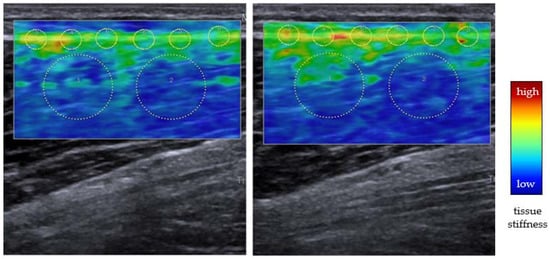

- Agten, C.; Buck, F.M.; Dyer, L.; Flück, M.; Pfirrmann, C.; Rosskopf, A.B. Delayed-Onset Muscle Soreness: Temporal Assessment with Quantitative MRI and Shear-Wave Ultrasound Elastography. Am. J. Roentgenol. 2017, 208, 402–412. [Google Scholar] [CrossRef]